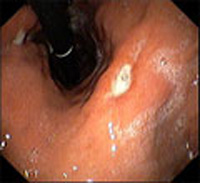

La úlcera péptica es una lesión como una herida que puede aparecer en la superficie de las paredes del tubo digestivo, principalmente en el estómago (úlcera gástrica) o en la porción más próxima del intestino delgado, que se conoce como duodeno (úlcera duodenal).